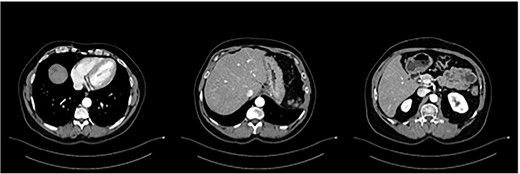

A 56-year-old male in good clinical condition presented at our outpatient clinic with pancreatic-body carcinoma and >25 synchronic LMs. A triple-phase computer tomography (CT) scan of the liver with intravenous contrast confirmed a 2.3-cm ill-defined hypodense lesion in the body of the pancreas and numerous ill-defined lesions, ranging from 1- to 3-cm in size, located in both liver lobes. Small peripancreatic lymph nodes were also noted (Fig. 1). A bone scan and whole-body CT scan were otherwise unremarkable. Serum levels of the tumor markers CA19-9 and CEA were 4730 U/ml and 138 ng/ml, respectively.

Pancreatic tail/body cancer (red arrow) with multiple liver lesions.